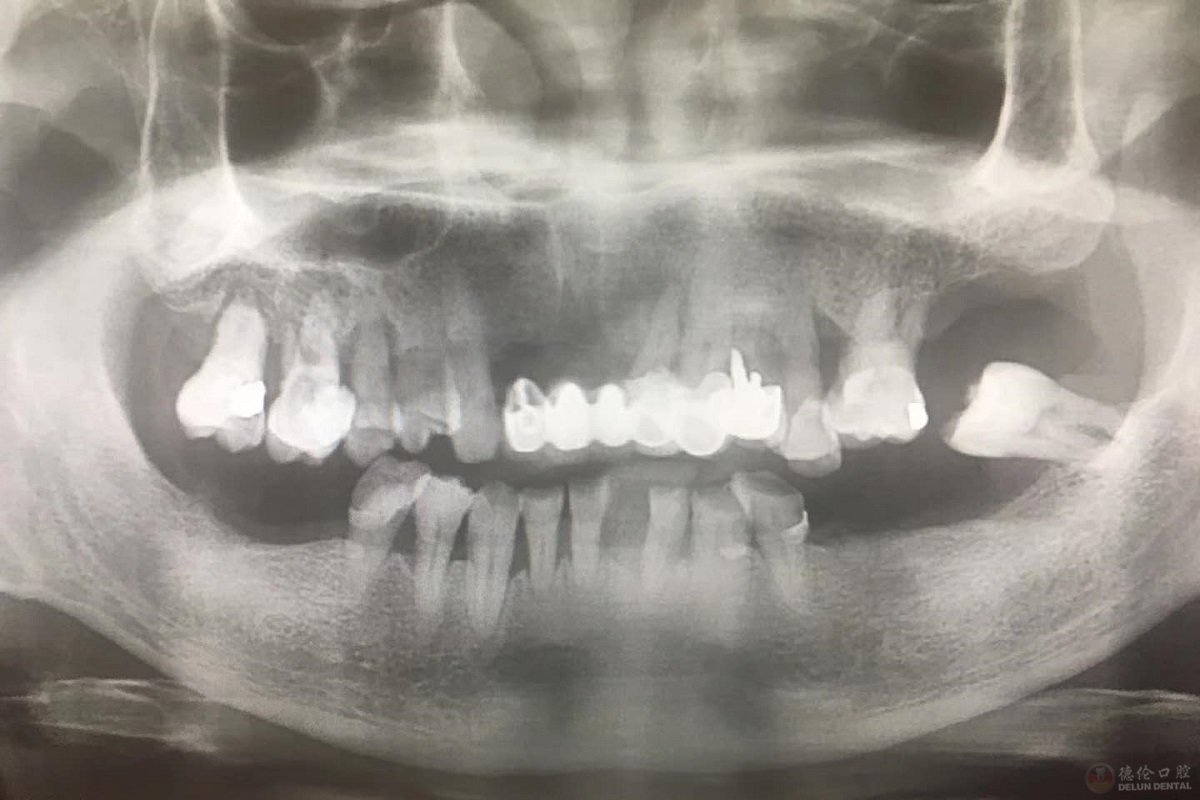

多荣先生因为牙周炎,导致多颗牙缺失,造成生活上的许多困扰,经朋友介绍,来到德伦接受治疗。刚进到德伦,多荣先生表示德伦的服务非常贴心与热情,陆医生仔细询问我的牙病史,给我拍片。

图为多荣先生种牙前CT片